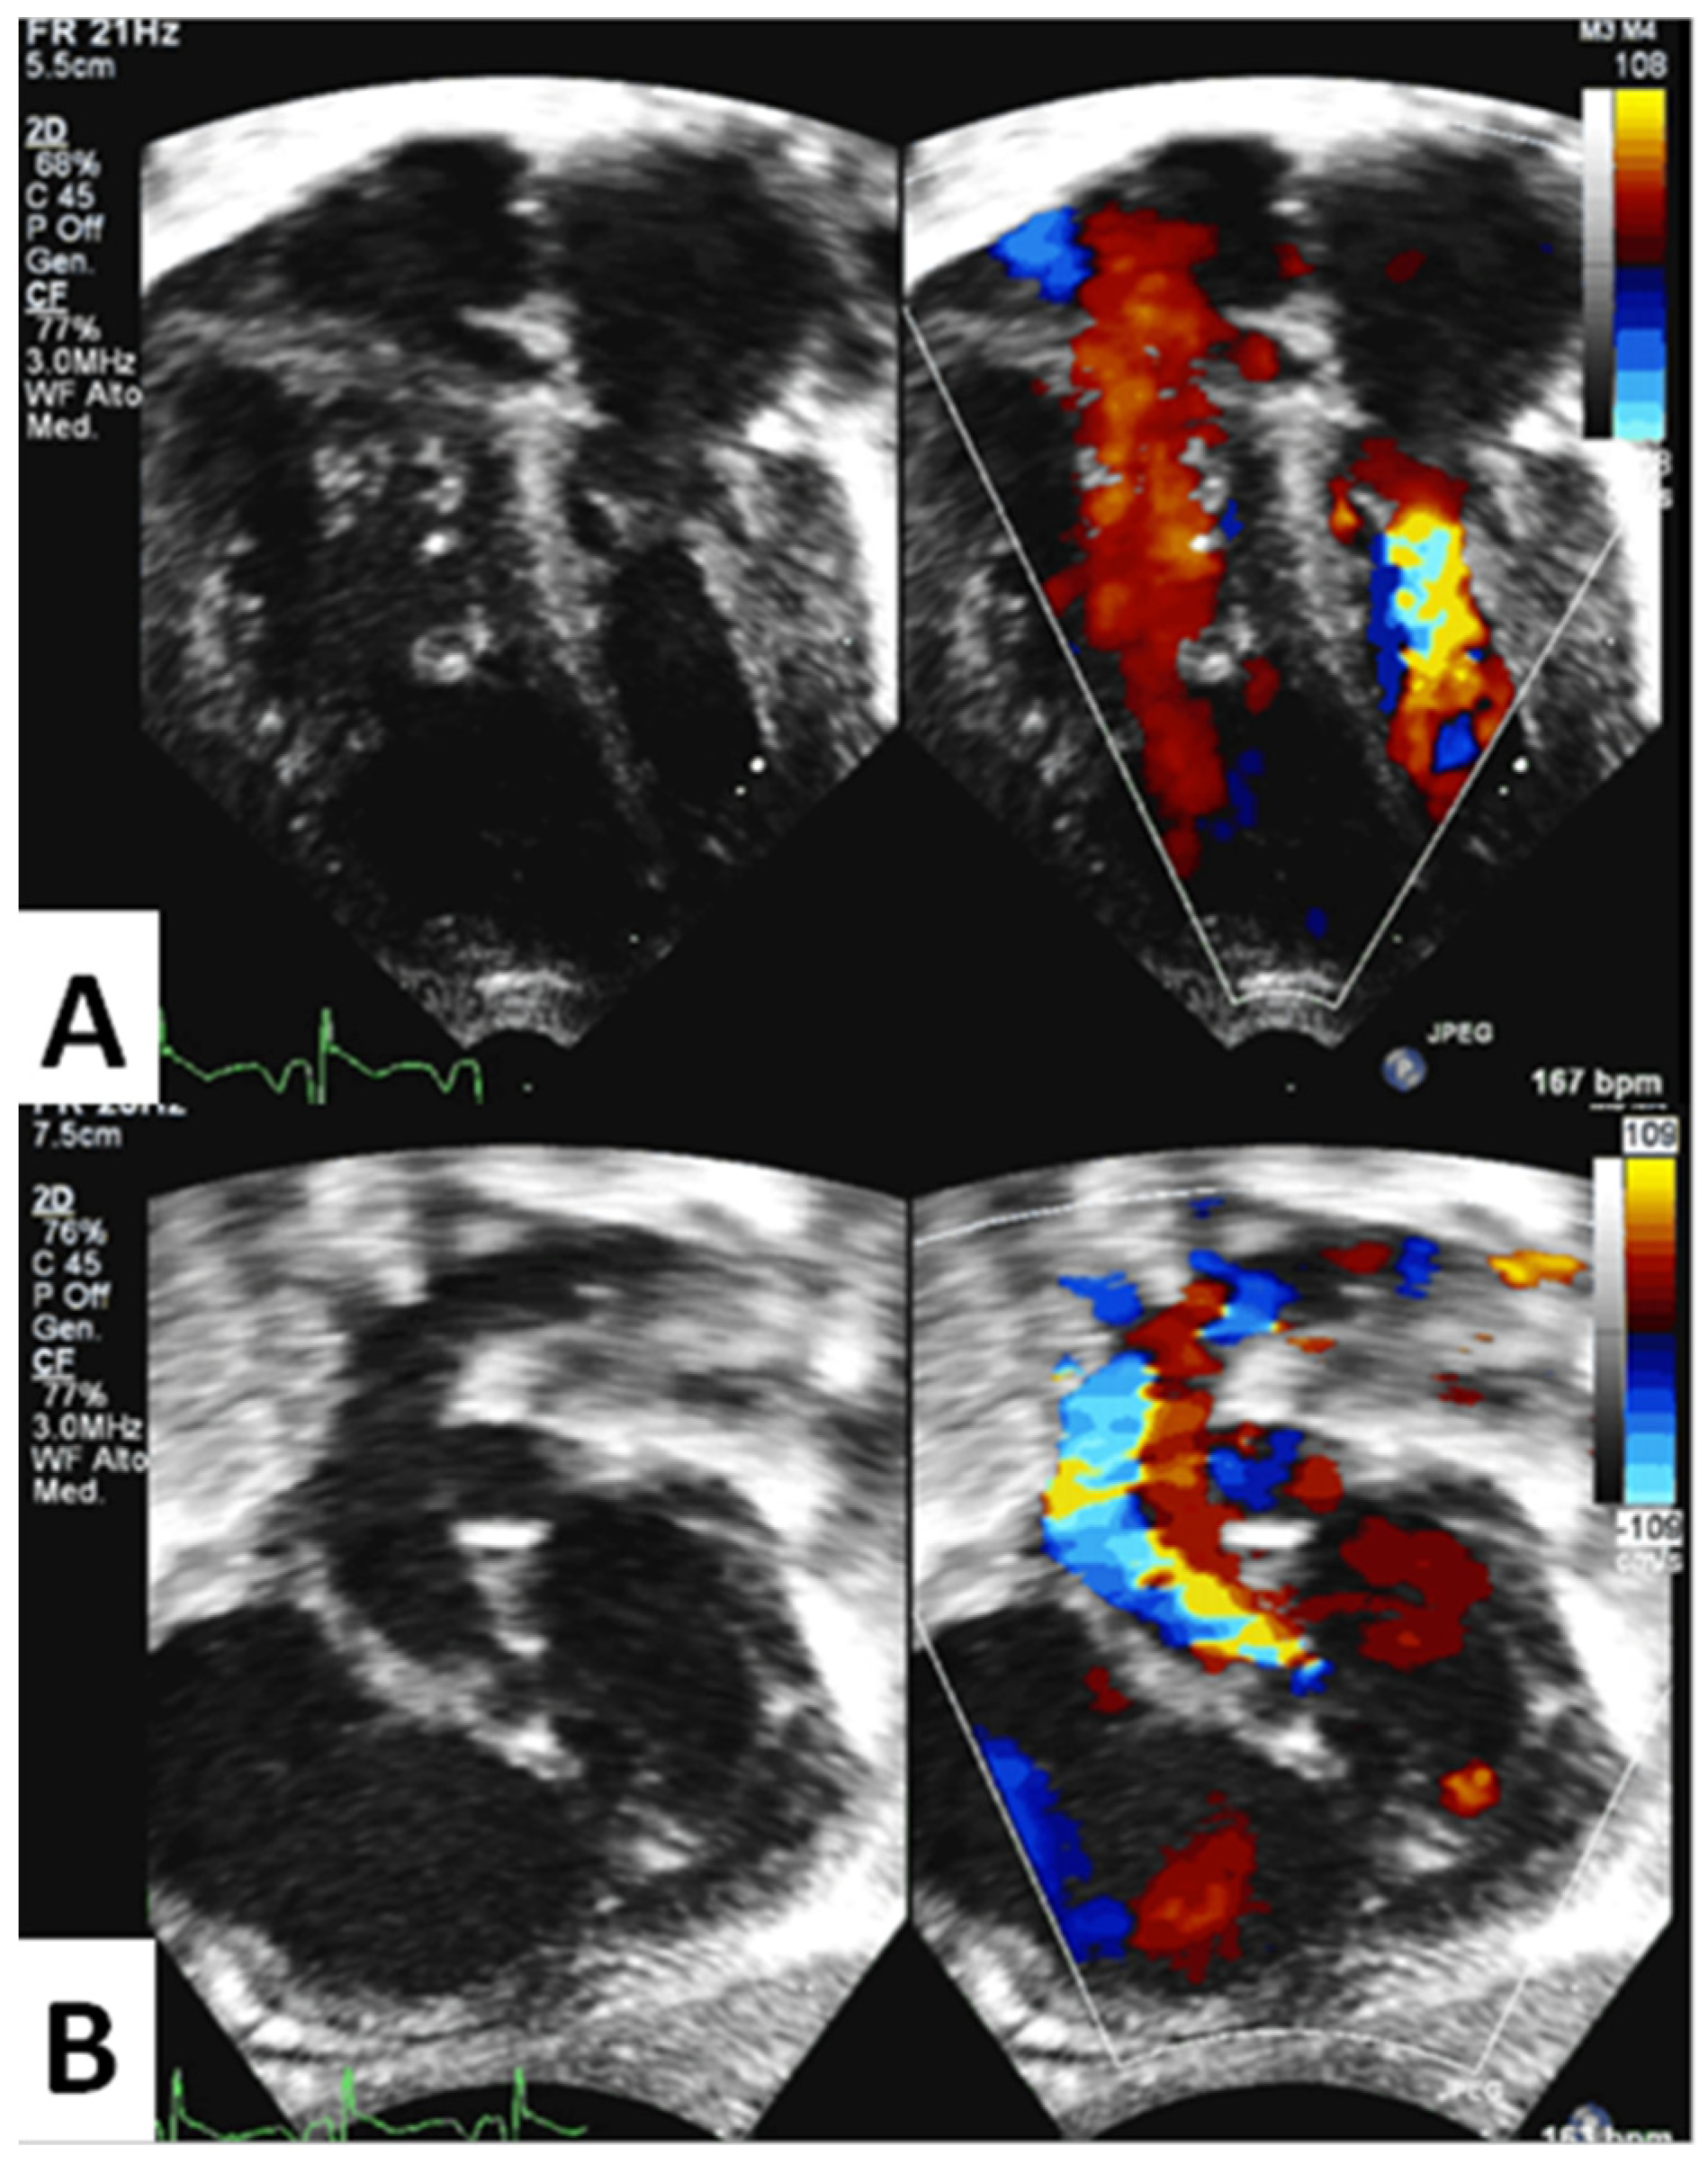

3.2. Qualitative Echocardiographic Evaluation